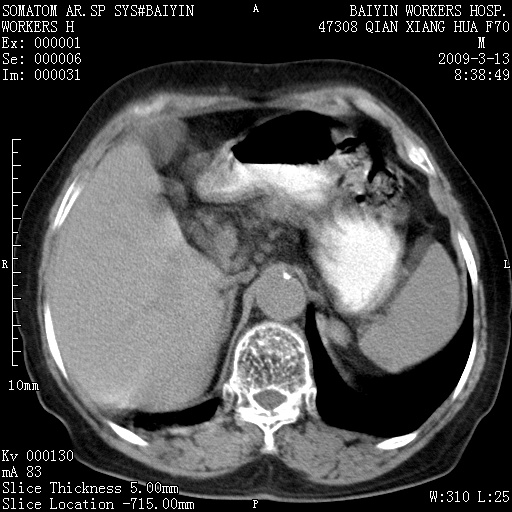

标题: CT18651:左肾上腺占位,请会诊! [打印本页]

标题: CT18651:左肾上腺占位,请会诊!

女,70岁,体检发现。

左侧肾上腺结节状软组织密度影;考虑肿瘤(肾上腺腺瘤?转移瘤?)。

左侧肾上腺占位,腺瘤?不除外转移。

左侧肾上腺占位,腺瘤可能。

左侧肾上腺占位,考虑腺瘤可能。